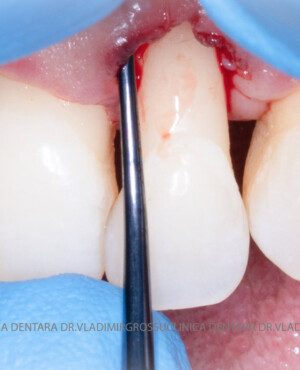

Adiția de gingie (gingivoplastia)

Aditia gingivală este o procedură chirurgicală ce corectează diverse probleme estetice și funcționale, cum ar fi recesiunea gingivală. În implantologia modernă, aditia de țesut moale este utilizată aproape în fiecare intervenție de inserție a implantului dentar pentru a asigura un aspect estetic natural și o bună integrare a implantului în cavitatea bucală.